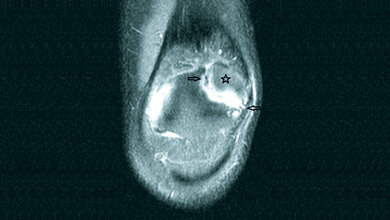

Anomalien und Normvarianten – Interne Veränderungen 2.18: Maldescensus testis

Der Maldescensus testis ist die häufigste genitale Malformation der Jungen und hat ein erhöhtes Risiko der Infertilität und malignen Entartung. Die Therapie mit humanem Choriongonadotropin ist oft erfolgreich, sonst die operative Behandlung mit Orchiopexie.

Schlüsselwörter: Maldescensus testis, Röntgen, Sonografie, CT, MRT